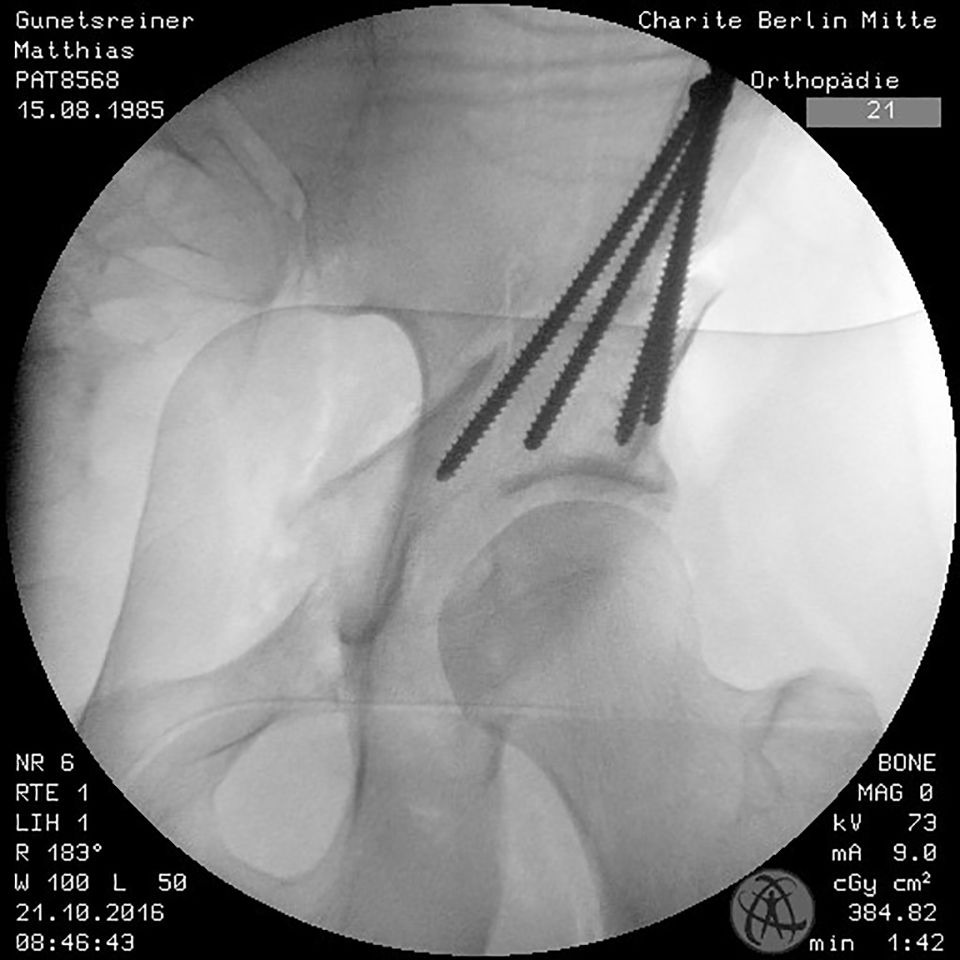

To avoid postoperative limitation in ROM or femoroacetabular impingement the freedom of motion after reorientation and before definite fixation of the acetabular fragment should be checked with minimum of 120° flexion and 30° internal rotation in 90° hip flexion. If an optimal acetabular reorientation and adequate ROM has been achieved the acetabular fragment is definitely fixed with four 4,5mm screws. The screw placement is verified with fluoroscopy to verify their extraarticular position (Fig. 16).

Arcoxia 90 mg is provided for 21 days postoperatively as a prophylaxis against heterotopic ossification. Antithrombotic medication Fragmin P forte 1x1 sc. is given until normal mobilization is achieved. Postoperative mobilization is performed under 50% weight-bearing with crutches for 4 weeks and progressed to full weight bearing until the 6th post-operative week. To check the stability of postoperative fixation and bone healing, an ap pelvic x ray should be obtained before full weight bearing (Fig. 19, 20). Low-impact sports can be initiated after the 6th postoperative week. No limitations regarding the ROM are given, but physical therapy is gently started after 2-4 weeks.